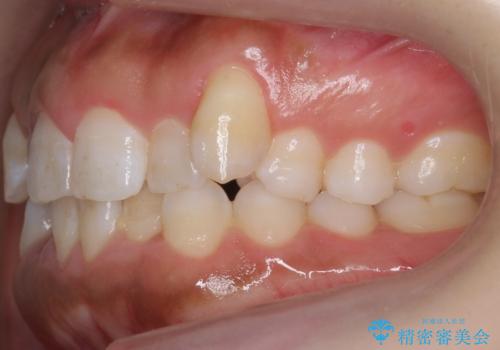

八重歯を非抜歯で マウスピースで治療 奥歯を後ろに下げてすき間を確保

- 八重歯を主訴に来院。

仕事柄ワイヤーが見えるよりはマウスピースで目立たなく歯並びを良くしていきたいとのことでした。

奥歯を後ろに下げてすき間を確保し、八重歯を引っ込めて並べる治療を行いました。